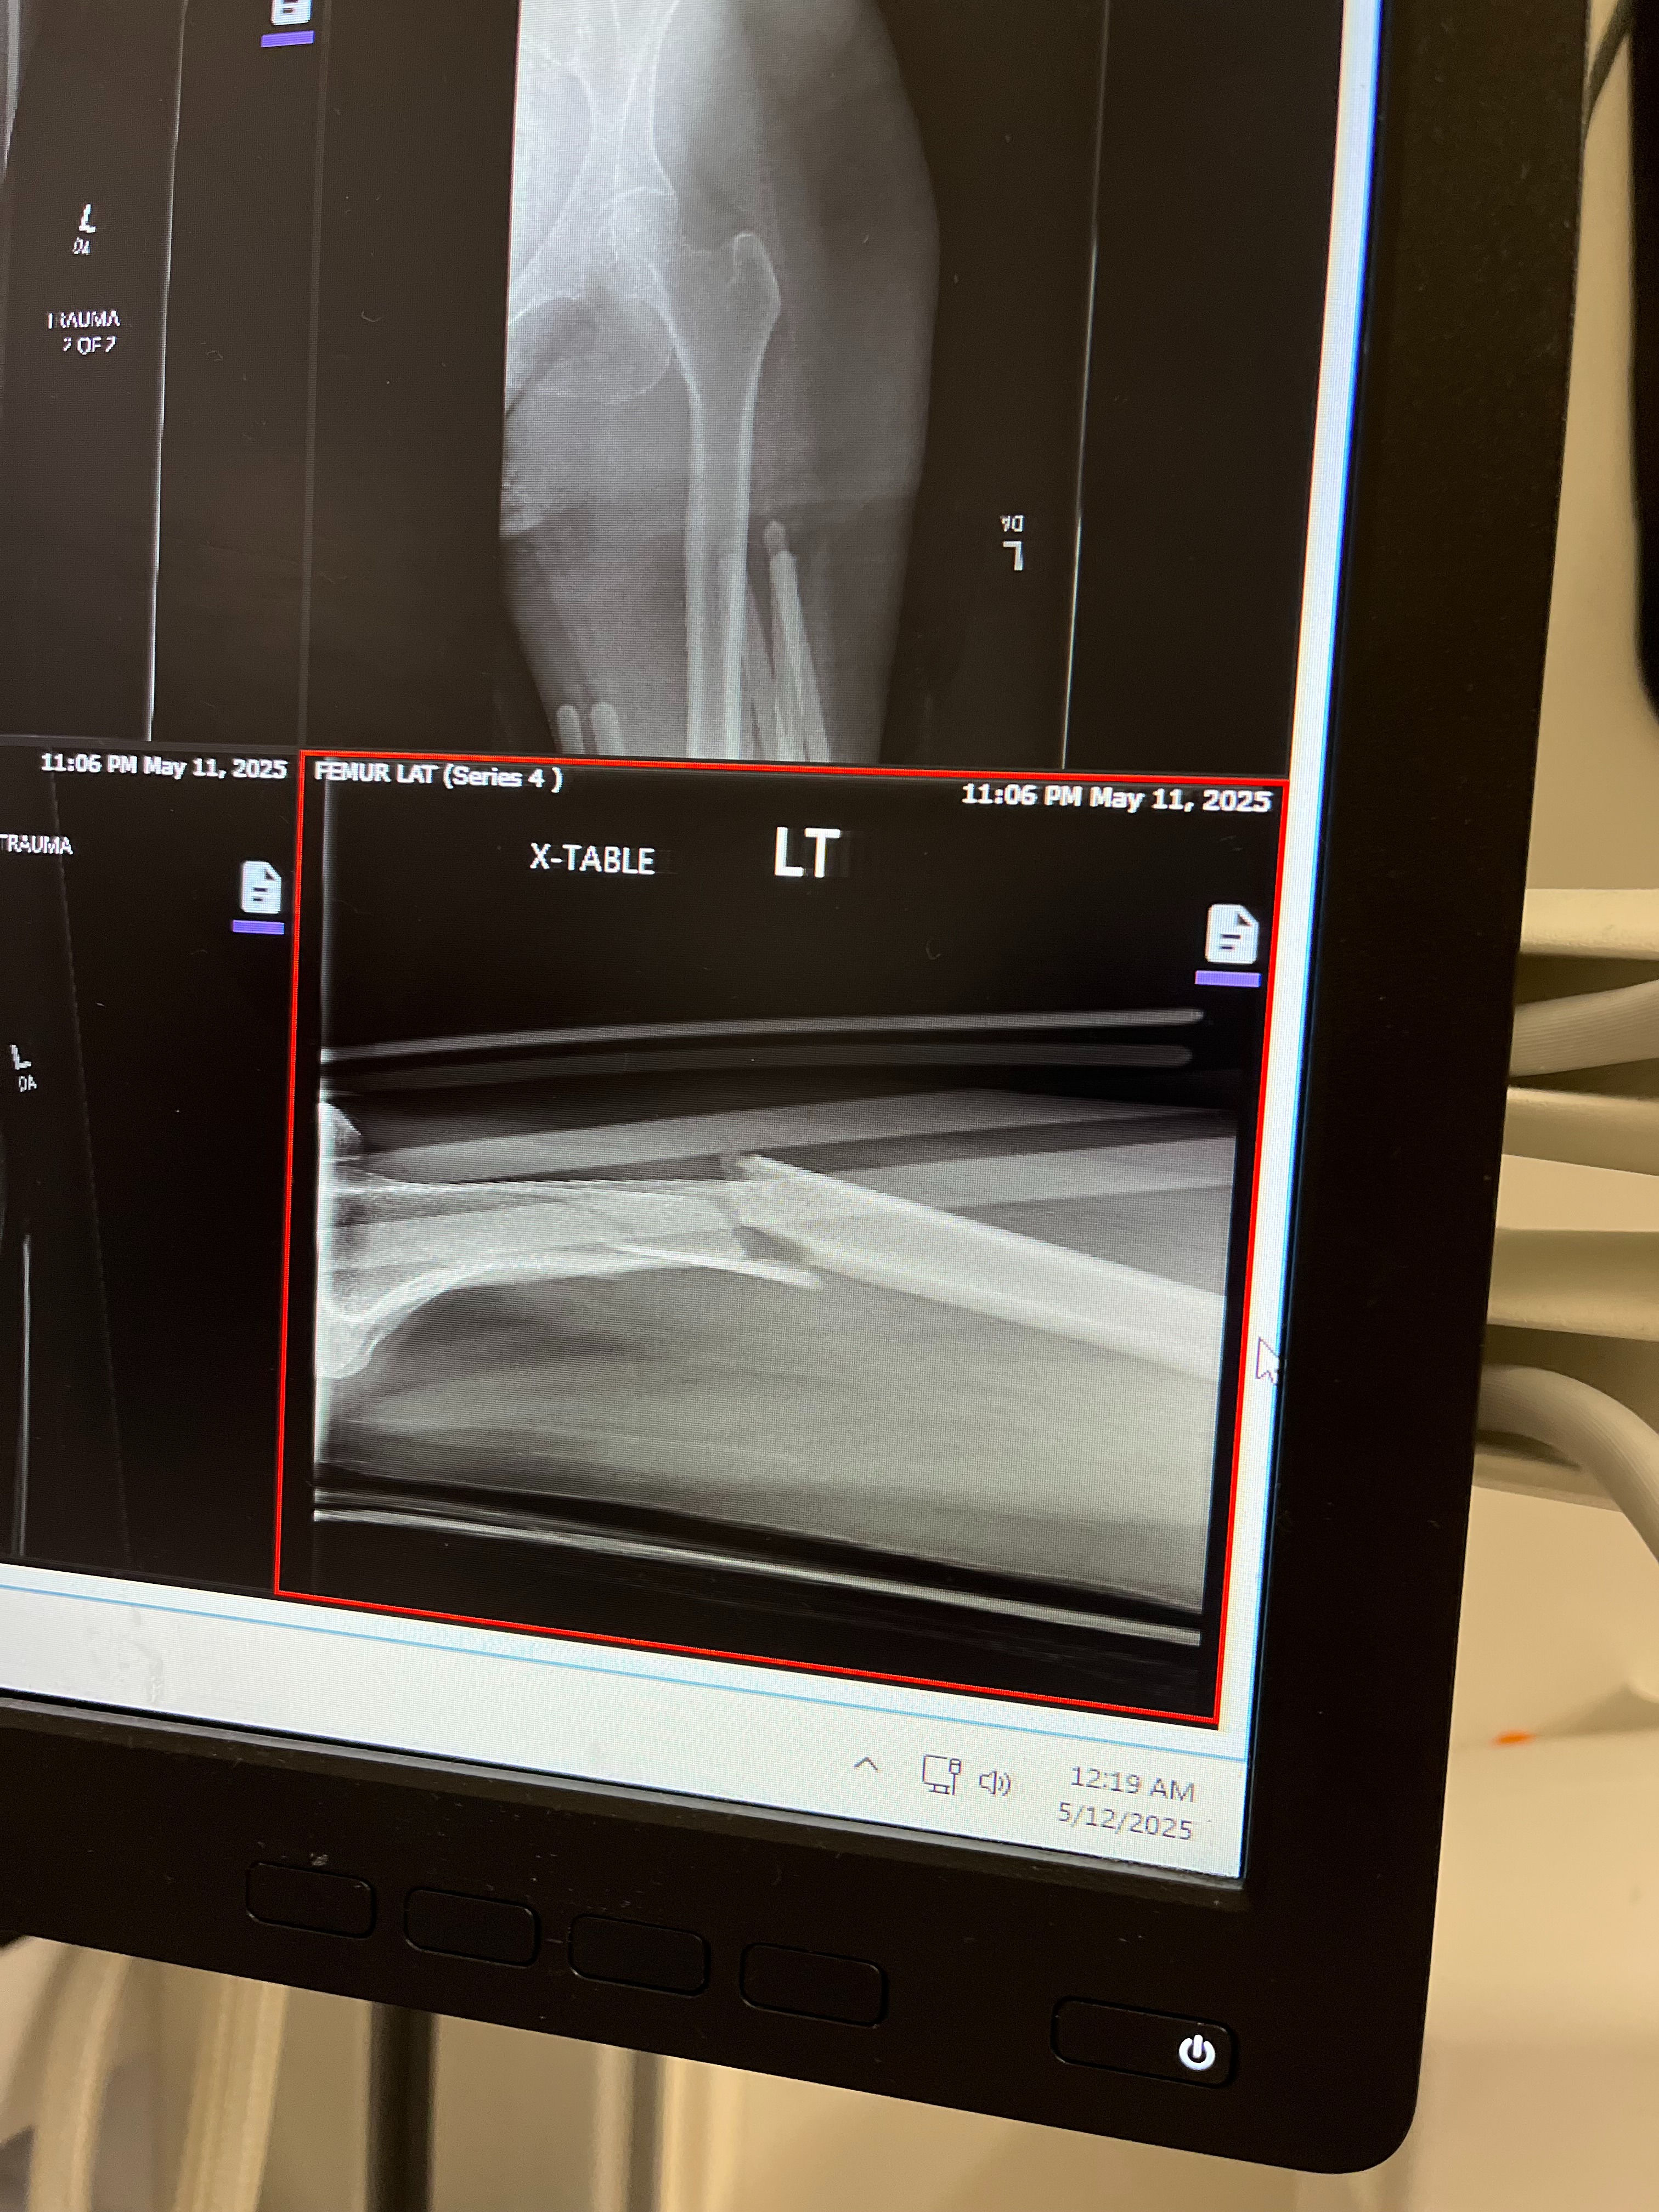

I am setting up this fundrasier for my mom Toniann due a traumatic accident that happened on Mother's Day that has left her in the hospital where she had emergency surgery to repair a broken femur.